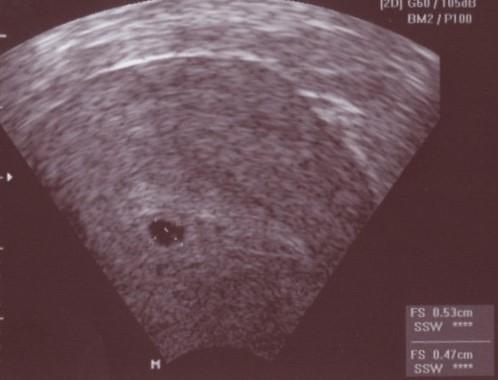

Jaa da bin ich wieder vom FA. Alles tip top in Ordnung. Fruchthöhle von gut 5 mm war zu sehen. Was mich total verwundert hat sogar schon mit Dottersack und der Doc meinte mit ganz viel Fantasie könnte man ein miniminimnini Embryo erahnen. Bin total glücklich. Nächster Termin am 23.11. mit schlagendem Herzchen und allen Blutuntersuchungen. LG Mareike

Schön, dass alles supi ist. Da ist man immer total erleichtert, oder?!?! So sah mein erstest US-Bild auch aus... Nur mein Fleck war kleiner.... 2mm.... Wünsche dir einen schönen Tag..... LG Tanja